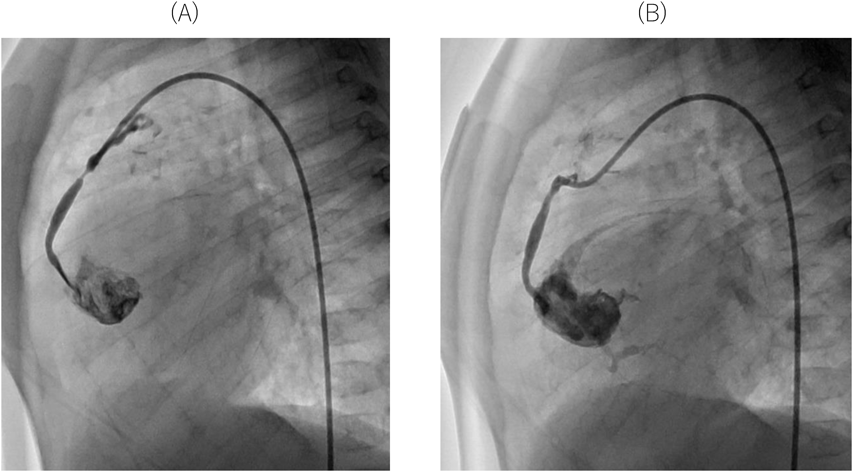

全冠動脈孔閉鎖を伴う純型肺動脈閉鎖症に対するAo-RV シャントの新たな治療戦略:Ao-RV シャントの有用性を類洞交通血流の変化で評価New Aorta-To-Right Ventricle Shunt Strategy for Pulmonary Atresia with Intact Ventricular Septum and Aortocoronary Atresia: Evaluation by Monitoring Sinusoidal Communication Flow